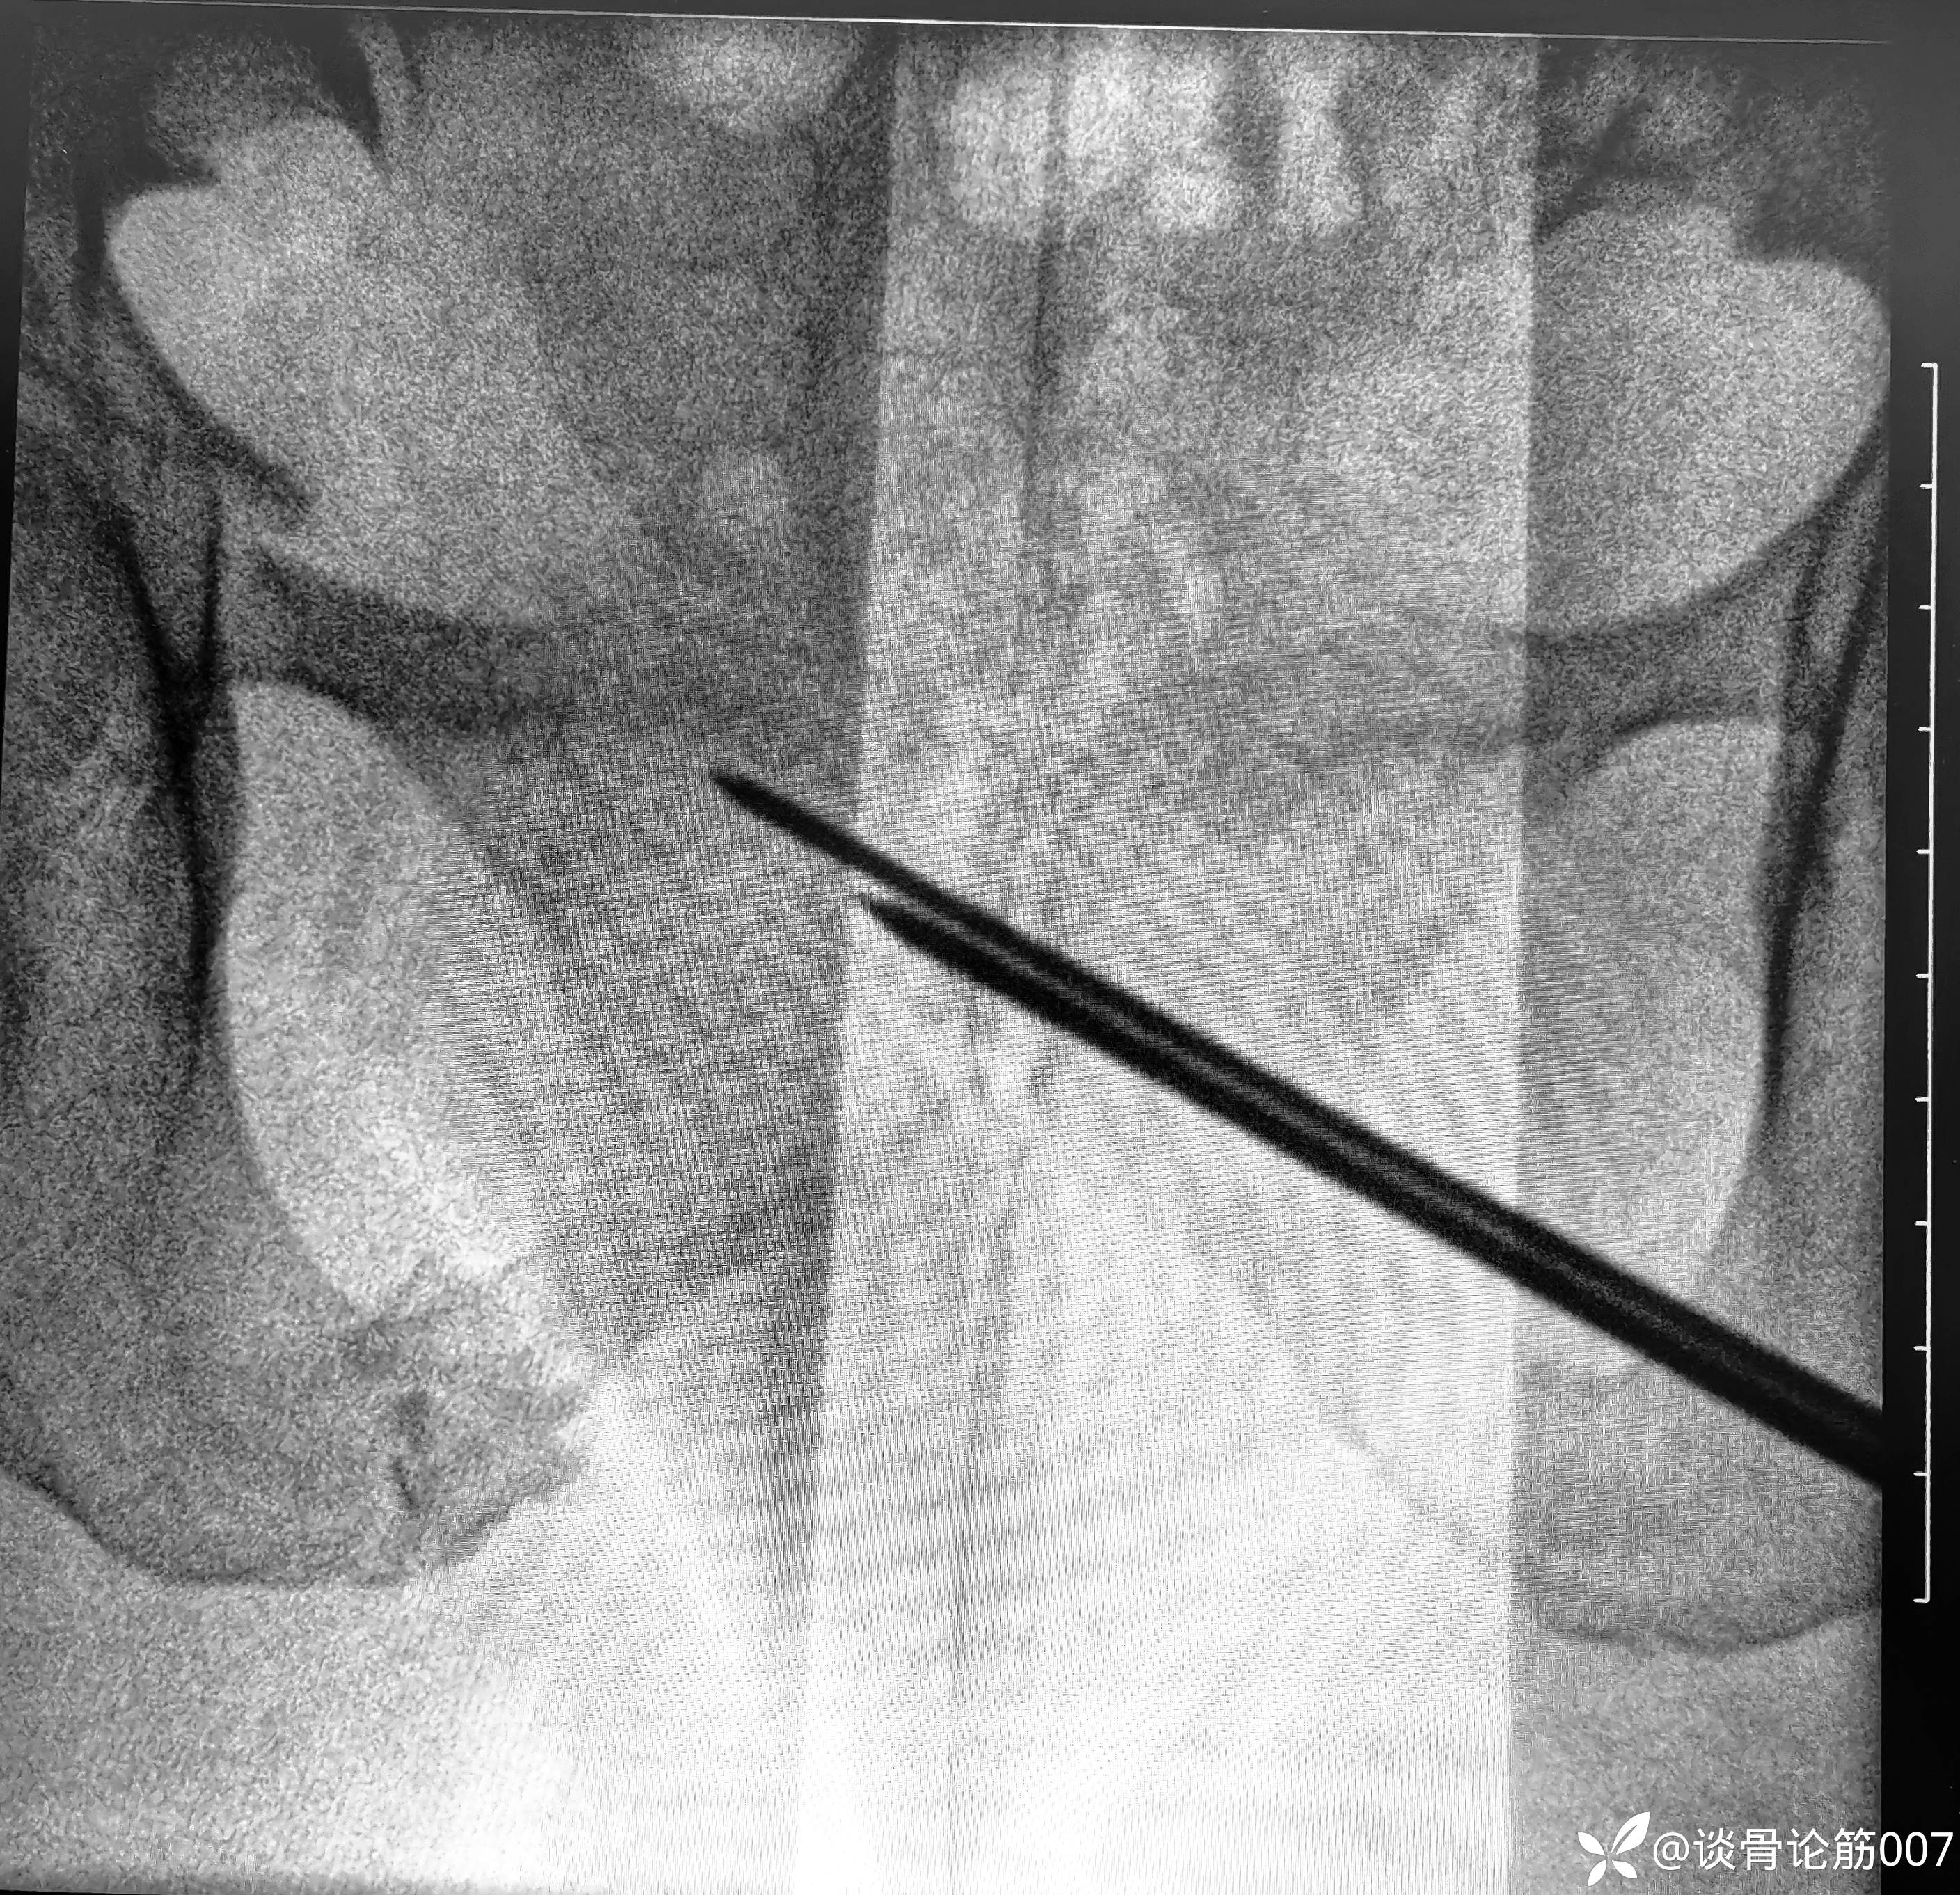

骨盆B型骨折,给予闭合复位骶髂螺钉+耻骨上支螺钉固定。

髂耻线比较高,骶髂螺钉相对简单一点

虽然术前进行导泄,通便,但腹部仍有积气,对透视还是有一定影响